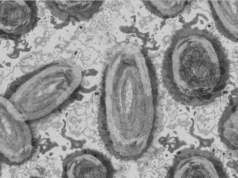

En Puerto Vallarta buscan casos sospechosos de la viruela de mono

Tras confirmarse un caso de viruela del mono, en Puerto Vallarta, las autoridades de Salud del estado de Jalisco instalaron un módulo de información...